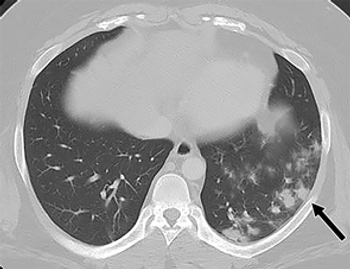

Abdominal CT scans show evidence of COVID-19 infection in lung base.